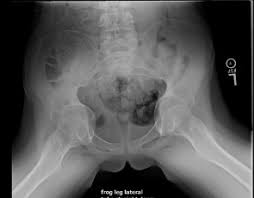

Marfan syndrome back pain. Despite these limitations studies describe that the prevalence of pain in patients with MFS is high varying from 47 to 92 and affecting several anatomic sites. Each had evidence of expansion of the central sacral spinal canal and enlargement of sacral foramina associated with extensive bony erosion. Low Back Pain in Marfan syndrome Patient Background and Purpose Marfan Syndrome MFS is an autosomal dominant disorder secondary to mutation of Fibrillin-1 that affects the bodys connective tissue.

Click below to download. Three patients complained of low back pain. MFS primarily affects the cardiovascular musculoskeletal and ocular systems.

Skeletal manifestations in the Marfan patient may develop or become more pronounced with age. The correlation between dural ectasia and back pain is uncertain.

Each had evidence of expansion of the central sacral spinal canal and enlargement of sacral foramina associated with extensive bony erosion. Three patients complained of low back pain. Experience Instant Relief From Back Pain With This New Product. Dural ectasia may cause low back and leg pain abdominal pain and headaches. A review of their medical history revealed that they had been diagnosed with Marfan Syndrome some years earlier. Not everyone who has spondylolisthesis also has Marfan syndrome but the likeliness of developing it is much higher for anyone who experiences this syndrome. It was descending down my anus and blocking my back passage so trying to empty my bowels was turning into a struggle which felt like an Olympic sport.